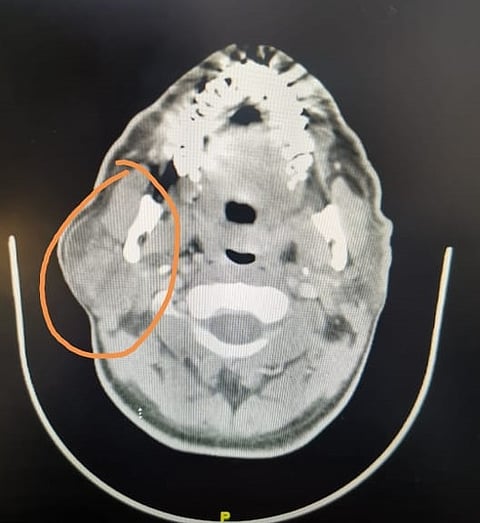

وتبيّن أن المريض يعاني من ورم حميد، وبعد إجراء الفحوص المعملية والإشعاعية المناسبة تقرّرت الخطة الجراحية المتقدمة والتي تحتاج إلى إجراء جراحي للغدة النكافية.